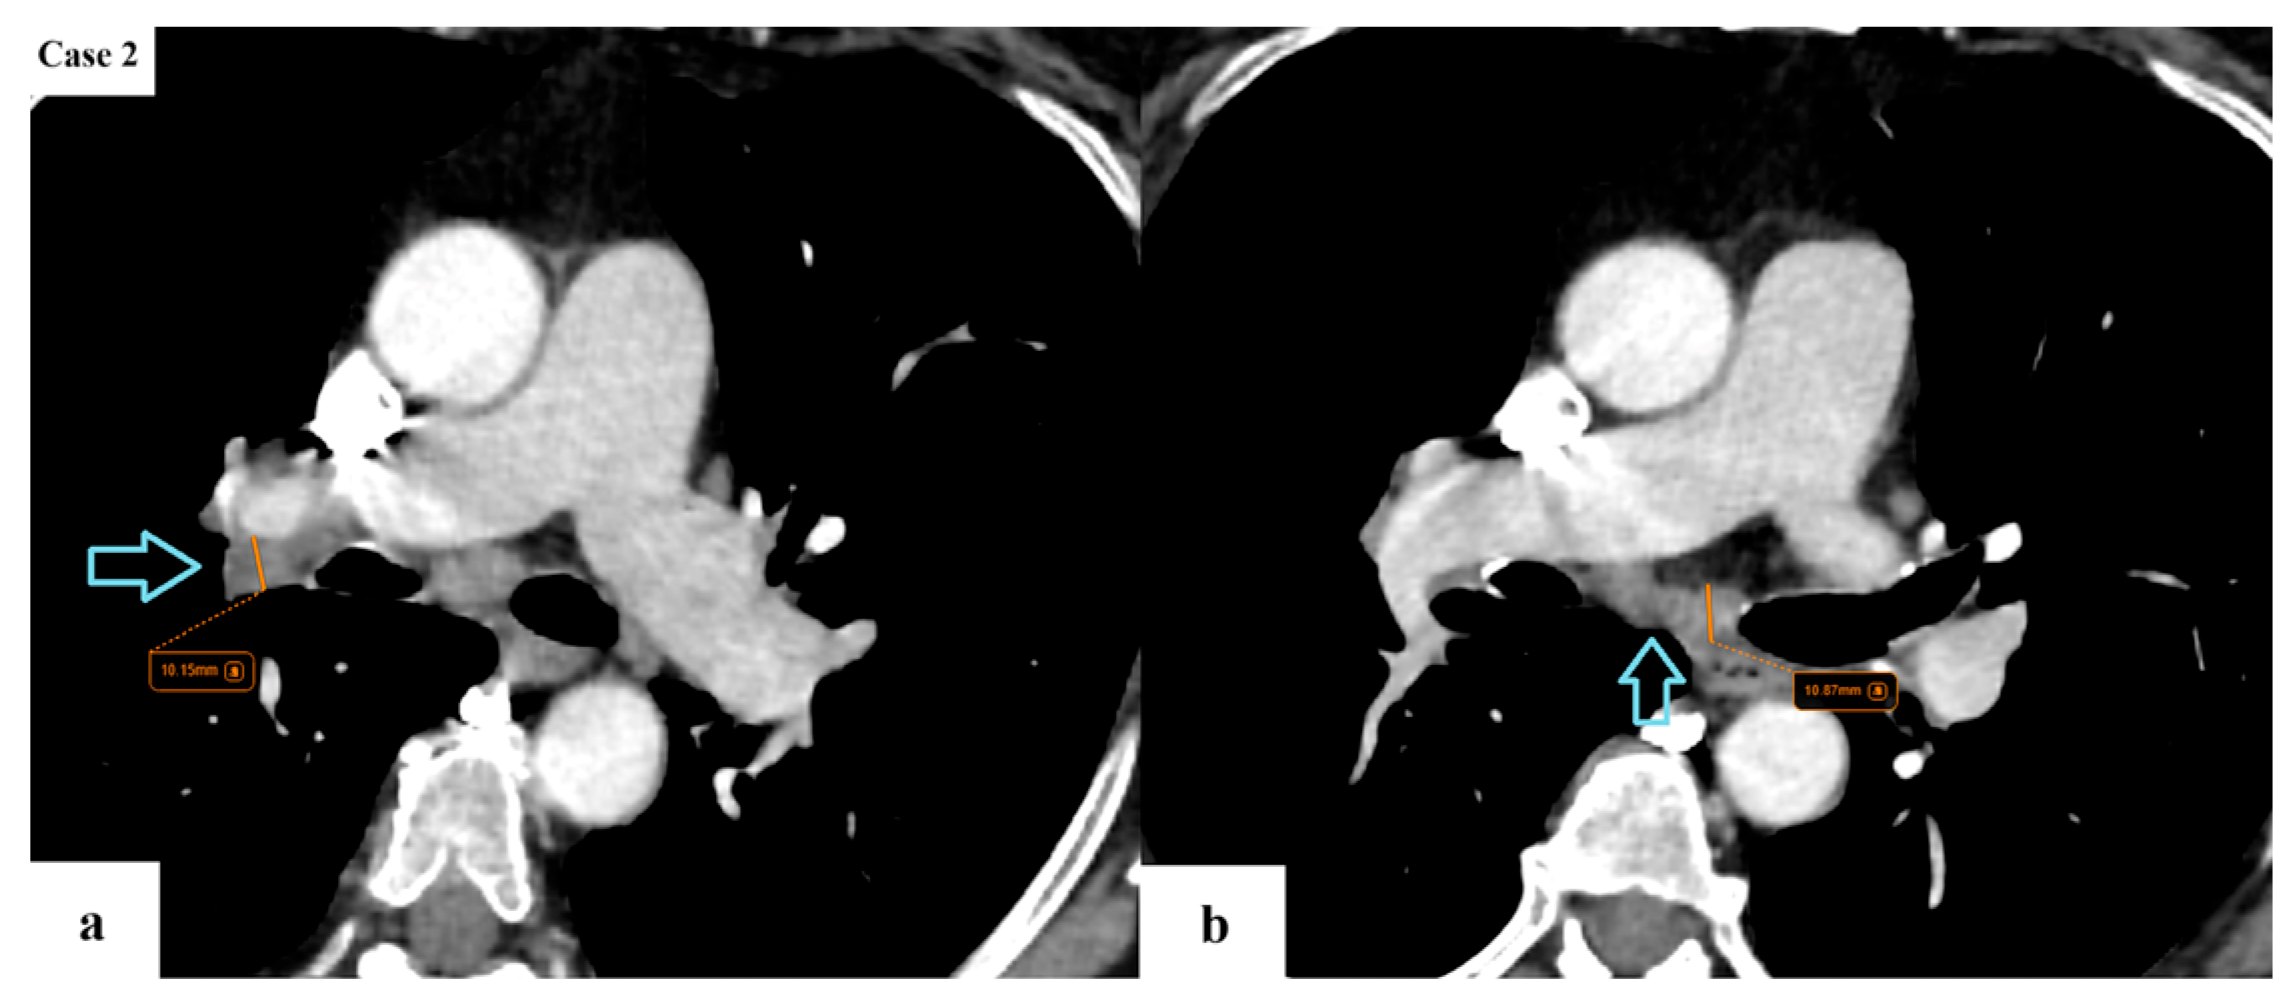

2.2. Data Collection and Imaging Evaluation

2.3. Staging Procedures

- N descriptor: subdivision of N2 disease into single-station (N2a) and multi-station (N2b);

- M descriptor: subdivision of M1c into M1c1 (multiple lesions in a single extrathoracic organ) and M1c2 (multiple lesions in multiple extrathoracic organs);